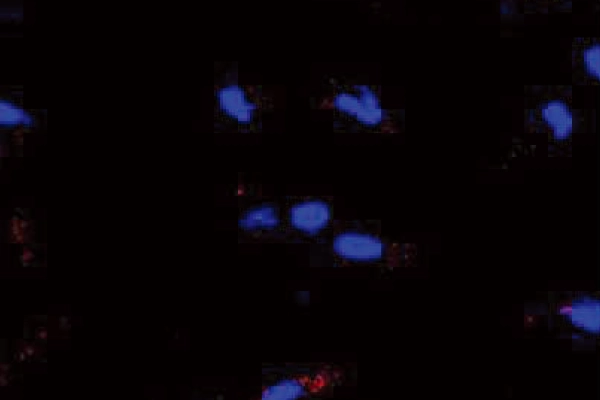

KEY 05

강력한 재생력

Ki67 Protein 발현 증가

엑소좀이 닿은 피부에 스스로 회복 신호를 깨우며 Ki67 단백질 발현 증가를 통해 눈에 보이는 세포 재생 효과를 입증하였습니다.

※ 엑소좀 사용량(×1011 particles), 본 자료는 한정된 조건에서 수행된 테스트 결과로, 개인의 피부 상태 및 사용 환경에 따라 차이가 있을 수 있습니다.